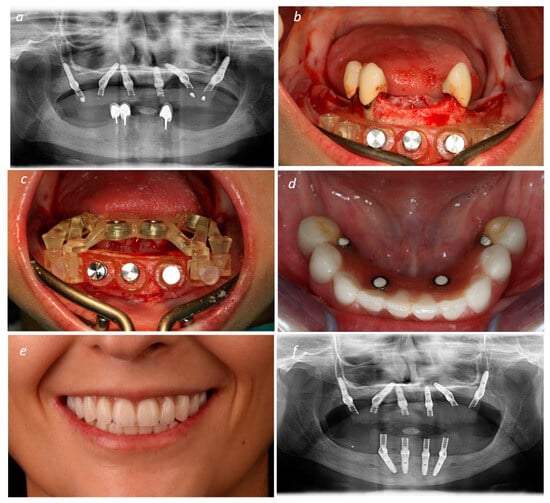

Description of the Technique

3. Results